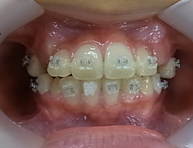

矯正治療前 矯正治療後

矯正治療前だと歯並びが悪いだけでなく、上下顎の骨が曲がっています。

早い時期に改善しないと、この骨格が自分の一生の骨格となってしまいます。。